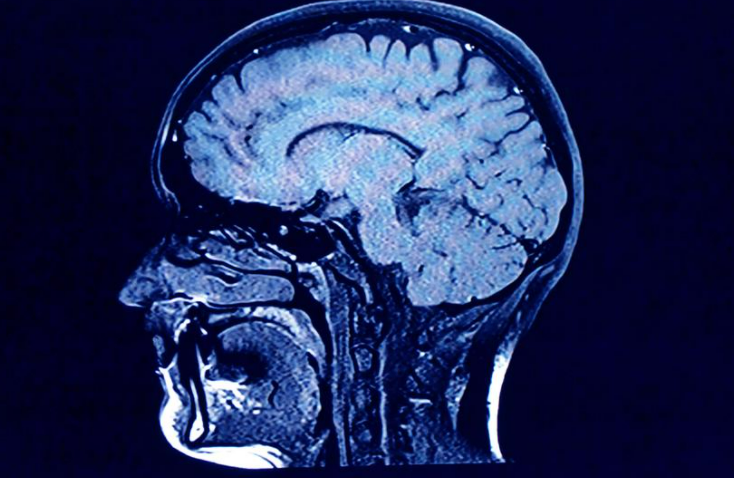

دراسة جديدة تؤكد تأثير كوفيد-19 السلبي على وظائف الدماغ وأنسجة المخ

اخبار استراليا- نٌشرت دراسة جديدة حول آثار كوفيد-19 على دماغ الإنسان وبيّنت أنه حتى المصابين بأعراض خفيفة كان لديهم شيخوخة دماغ أسرع وتغيرات في الوظائف الدماغية.

وأفادت الدراسة أنه بالمقارنة بين أدمغة المصابين وغير المصابين بالفيروس، تبيّن أن كوفيد-19 يشوّه أنسجة المخ ويسبب فقدان المادة الرمادية، كما يرتبط كثيراً بفقدان حاسة الشم.

قالت الدكتورة داود أن كل مصاب فقد حوالي 0.2 أو 0.3 في المائة من المادة الرمادية في الدماغ في كل سنة، و0.2 إلى 2 في المائة من أنسجة المخ أكثر من الذين لم تنتقل إليهم العدوى.

تراوحت أعمار المشاركين بين 50 و80 سنة، وشمل الفحص تصوير الدماغ واستعمال أنشطة ذهنية لمراقبة الإدراك والوظائف الدماغية لدى المشاركين، وتوضّح تراجع المستوى الإدراكي لدى المصابين.

لم تتوصل الدراسة إلى كيفية التأثير الدقيق للفيروس على الدماغ لكنها كشفت ارتباطاً وثيقاً بين العدوى وتراجع الوظائف الدماغية.